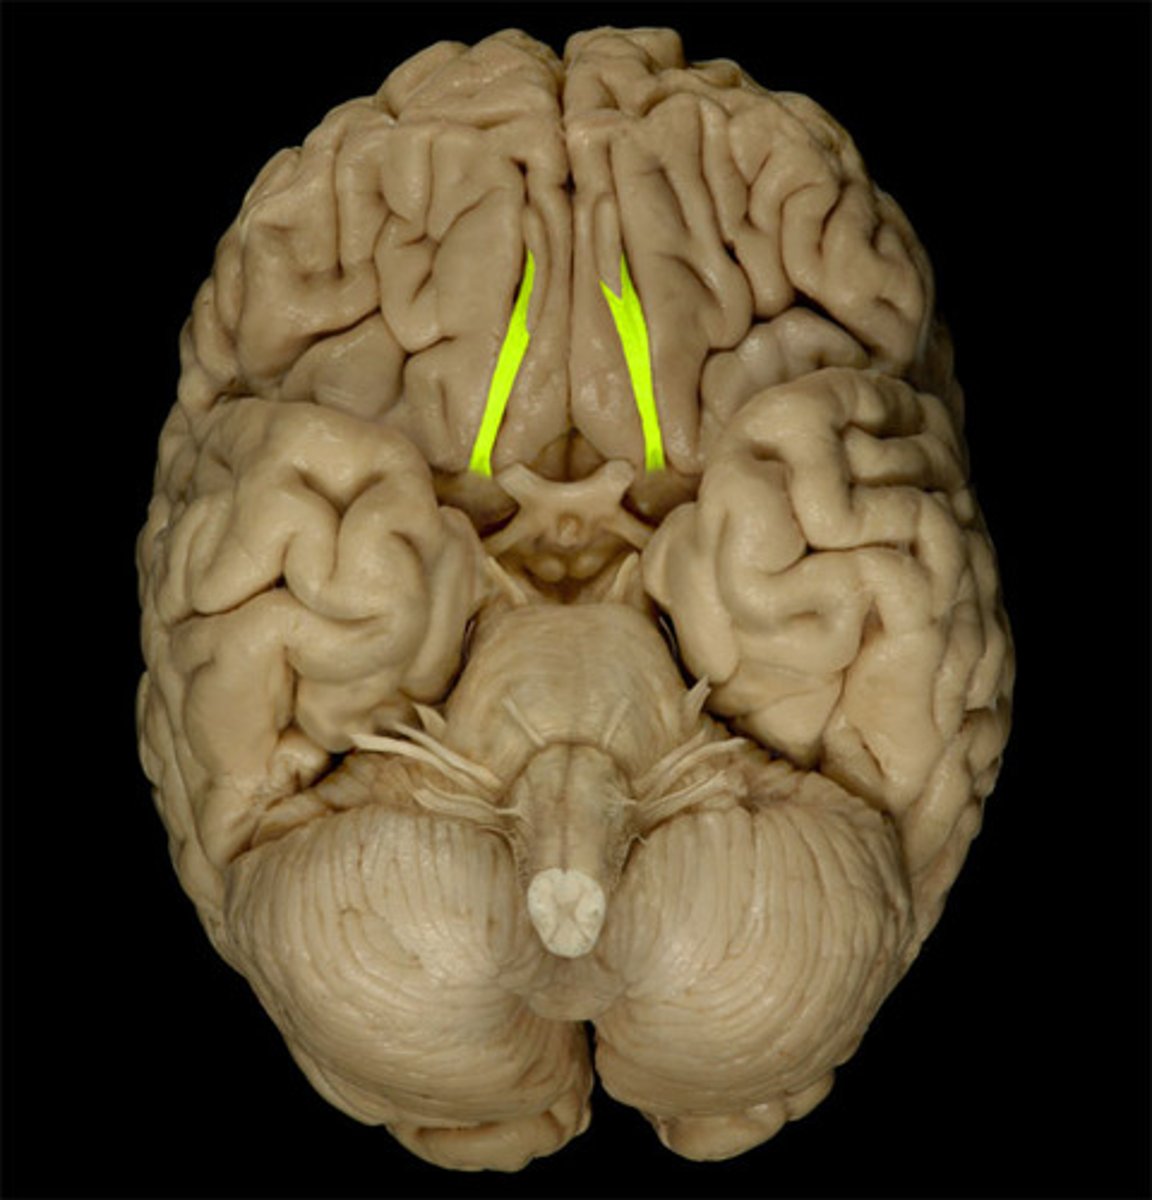

Superior Dorsal View of brain

Gyri

Sulci

Longitudinal Cerebral Fissure

Frontal Lobe

Parietal Lobe

Occipital Lobe

Central Sulcus

Lateral Sulcus

Somatomotor Area

Somatosensory Area

Cerebellum

Olfactory Bulb

Optic Chiasm

Mammillary Bodies

Pons

Medulla Oblongata